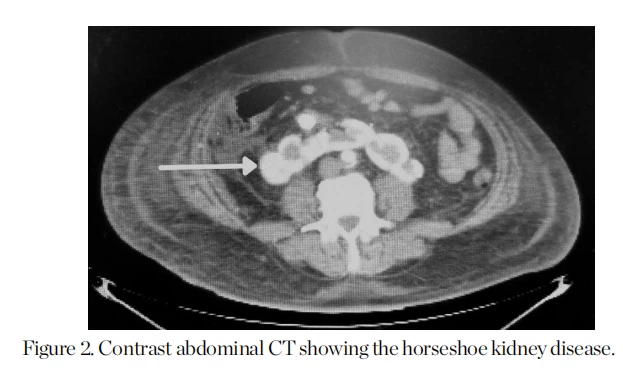

Se consultó al servicio de urología por nefrolitiasis y posible procedimiento de litotricia. Se solicitó tomografía computarizada (TC) abdominal contrastada y angiografía renal, encontrando riñón en herradura y placas ateroscleróticas ocluyendo la luz arterial (Figuras 2, 3 y 4).

Como parte del abordaje del riñón en herradura, a nuestro paciente se le realizaron imágenes para analizar la anatomía del riñón y sus vasos, que mostraron la presentación clásica de fusión de los polos inferiores del riñón y nefrolitiasis bilateral. El diagnóstico generalmente se realiza accidentalmente al realizar imágenes no invasivas. por otra razón".{{0}} En estos pacientes se ha utilizado tratamiento quirúrgico, como litotricia por ondas de choque, ureteroscopia, nefrolitotomía percutánea y laparoscopia.0 La litotricia era un plan posible debido a la nefrolitiasis, pero la placa aterosclerótica aortoilíaca encontrado en los estudios de imagen.